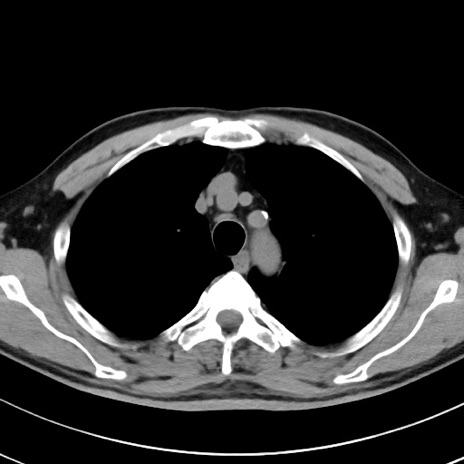

【腹部TIPS】症例29 参考症例 CT(横断像)

症例

70歳代男性